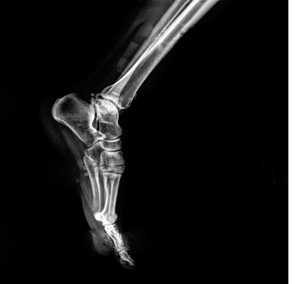

Для диагностики состояния стопы применяют рентгенологические методы, КТ и МРТ. Рентгенограмму делают в нескольких проекциях. На рентгене видны кости стопы и голеностопного сустава, плотность костей, а также состояние свода стопы. С помощью рентгенологических методов определяют переломы костей, деформации пальцев, дегенеративно-дистрофические заболевания суставов.

![]() | Рис. 13. Рентгенограмма стопы в состоянии свободного виса. При сгибании в голеностопном суставе продольный свод стопы увеличен |